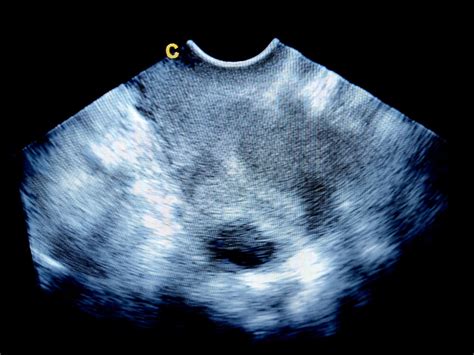

Umiestnenie placenty môže byť rôzne a je spoľahlivo identifikovateľné pomocou ultrazvukového vyšetrenia, ktoré je súčasťou bežnej tehotenskej starostlivosti. Každá poloha má svoje špecifiká, hoci vo väčšine prípadov nejde o dôvod na obavy.

Z hľadiska pôrodu predná placenta nemusí znamenať žiadne obmedzenie. Dôležité je sledovať, kde presne sa nachádza - ak je umiestnená vysoko, je to v poriadku. Problém môže nastať len v prípade, ak sa nachádza príliš nízko a zasahuje ku krčku maternice. V takom prípade lekári situáciu dôkladne sledujú. Predná placenta tiež môže mierne sťažiť niektoré vyšetrenia, napríklad ultrazvuk, pretože môže prekrývať obraz plodu. Diagnóza prednej placenty sa zvyčajne stanoví počas bežných prenatálnych ultrazvukových vyšetrení, ktoré sa zvyčajne vykonávajú v prvom alebo druhom trimestri tehotenstva.